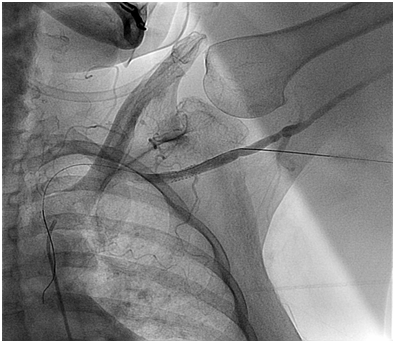

One clinical implication of the ubiquitous nature of Type III arches in our very elderly aortic stenosis patients relates to percutaneous access for interventions such as TAVR. In specific, with the left arm hyper extended over the head, the trajectory of the left axillary and left subclavian arteries falls along the trajectory of a Type III arch (Figure 3). This trajectory makes an axillary approach an attractive alternative to trans: apical and trans: aortic approaches in patients with advanced lung disease or severe peripheral artery disease (PAD) who are not good candidates for either transfemoral or transapical/transaortic approaches. Finally, this information coupled with the fact that axillary artery size is quite comparable to femoral artery size in most patients,8,9 a totally percutaneous left axillary artery approach utilizing a double Per close large bore arteriotomy closure at the end of procedure is highly feasible for a totally percutaneous TAVR as demonstrated by Shäfer et al.10 and also for totally percutaneous Impella device insertion and removal (Figures 4A to 4E) as shown by our group.8

Figure 4A Axillary Artery access with micropuntcure needle utilizing roadmap guidance obtained by injecting contrast through a catheter advanced from R common femoral artery to the L subclavian artery.